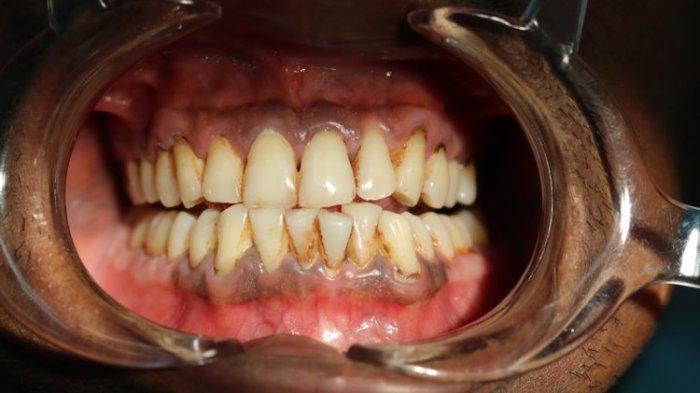

Kondisi warna gusi yang lebih gelap dikenal dengan hiperpigmentasi gingiva.

Pigmentasi gingiva sebenarnya bisa dikategorikan sebagai anomali, meskipun semuanya tidak terasa mengganggu sang pemilik raga.

Terlebih apabila warna-warna gusi mengarah ke warna gelap sekali, semisal warna coklat menuju ke hitam.

drg. Anastasia menyampaikan bahwa ada juga yang warnanya menyebar atau difuse, dan ada juga yang modelnya seperti titik-titik dari warna keunguan, kecoklatan, kehitaman, termasuk seperti helaian tipis yang tampak pada gusi.

Pigmentasi merupakan perubahan warna gingiva karena berbagai lesi atau kondisi terkait etiologi baik endogen maupun sesuatu yang sifatnya eksogen.

Terkait hiperpigmentasi atau pewarnaan pada gingiva atau gusi ada yang tergolong faktor endogen dan eksogen.

Faktor endogen biasanya berasal dari kondisi perubahan terkait melanin, bilirubin, dan zat besi.

Pada beberapa penyakit sistemik, semisal kondisi penyakit addison, HIV dan banyak jenis penyakit lain juga memunculkan anomali pada gingiva atau gusi.